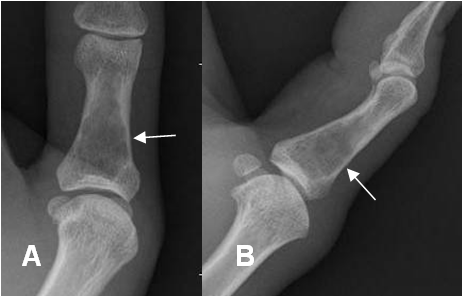

Fig 86. Encondroma.

A: Rx AP y B: Rx lateral. Imagen lítica de bordes mal definidos y con leve expansión a nivel del pulgar, por encondroma.